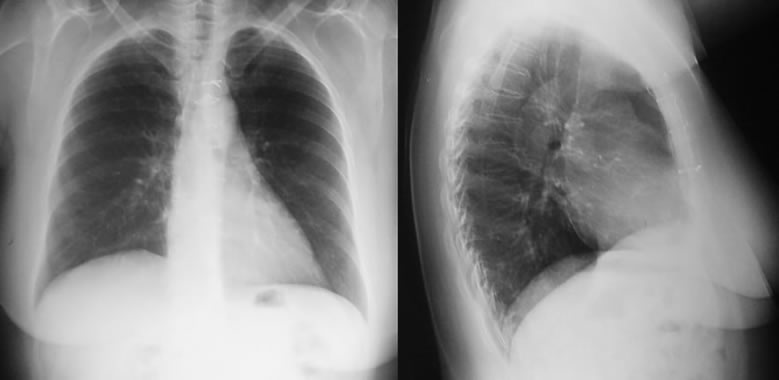

Quiste pericardico, Radiografia de Ingreso

Rx. Tórax al momento de Ingreso. Una radiopacidad homogénea densa, redondeada, en hemitorax derecho; de base en cara medial mediastinica con la silueta cardiaca y convexa en su cara externa derecha, rodeada por parenquima pulmonar sano y no esta adherida al diafragma ni al seno costofrénico derecho el cual se observa libre, pareciendo formar parte con la silueta cardiaca la altera de manera, como si se tratase de una cardiomegalia, el botón aórtico se aprecia borrado, no hay derrame pleural y la conformación de la caja torácica se observa dentro de la normalidad.